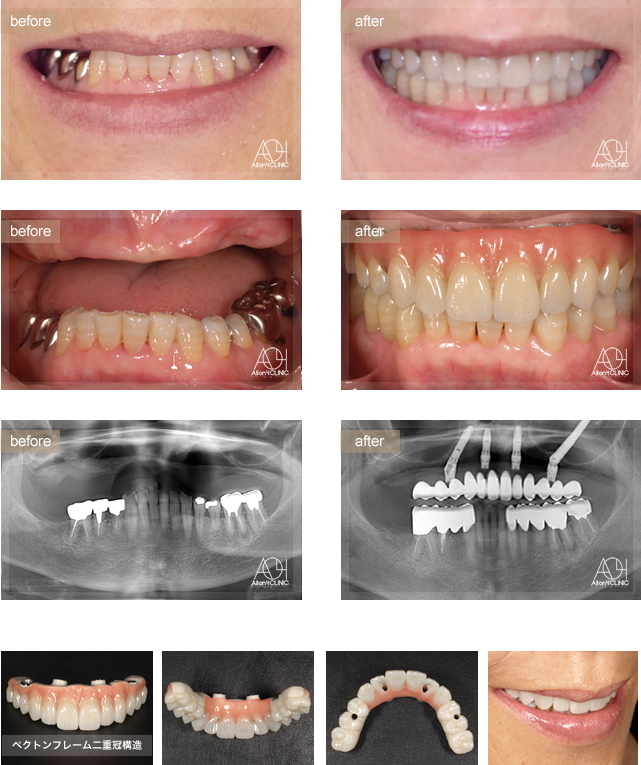

Age : 67

Sex : Female

- Maxilla All-on-4

上顎左側後方Zygomaインプラントを使用。上顎上部構造はペクトンフレーム、

二重冠構造(歯肉:アクリリックレジン 歯:フルジルコニア)を採用。